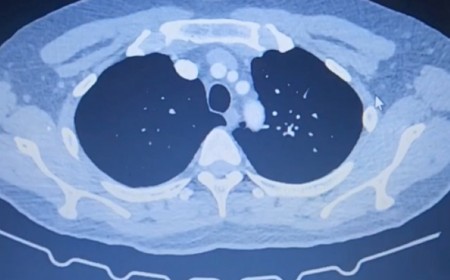

TÔI KHÔNG NGỜ ĐẾN MÌNH CŨNG BỊ NHIỄM SÁN CHÓ

Ngày 01 tháng 4 năm 2023 Phòng khám Quốc Tế Ánh Nga tại số 443 Đ. Giải Phóng – Thanh Xuân - Hà Nội đón một vị khách tên N.T.K.S đến từ Phố Hàng Bông – Q. Hoàn...